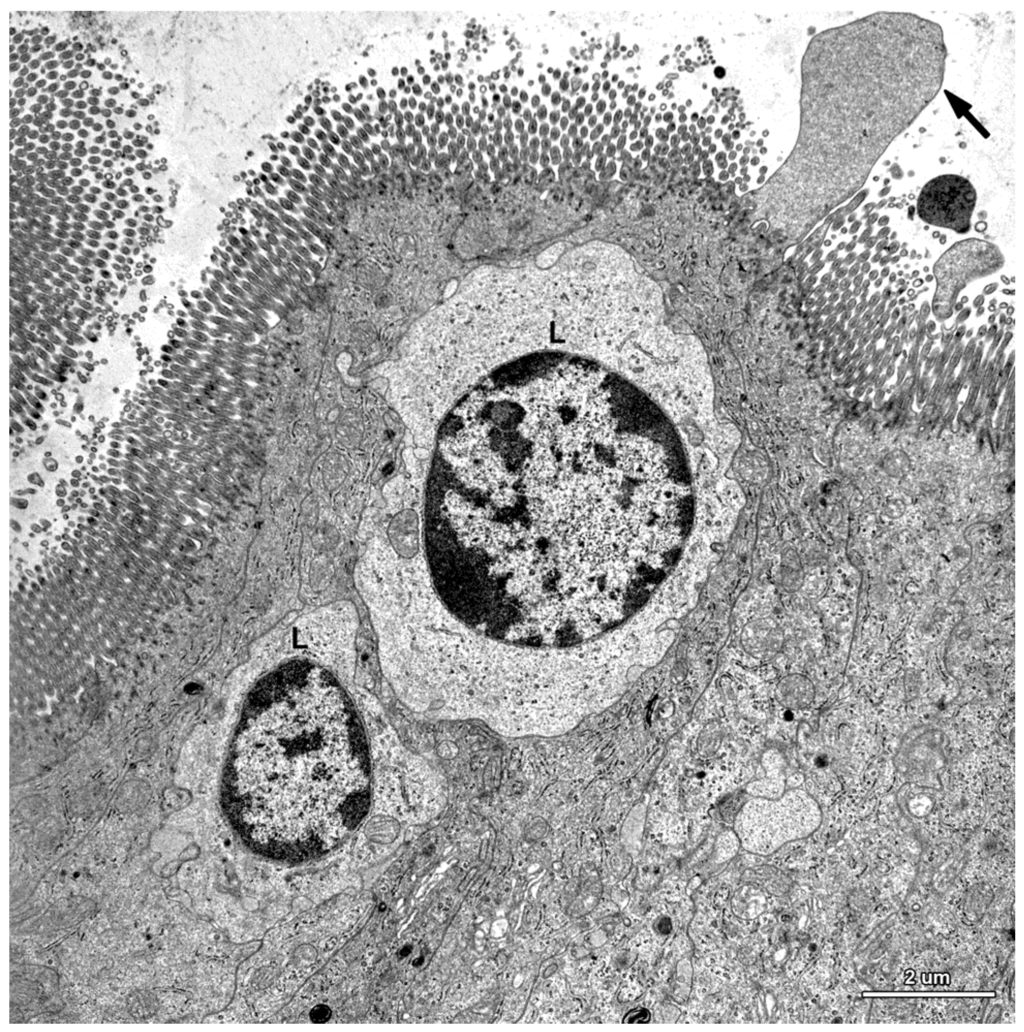

Figure 7.

Ultrastructure of the jejunal mucosal epithelium in a pig that received ZEN for one week. (A) Drop-like protrusions extending from the apical surface of the enterocytes; (B) Lymphocytes (L) between epithelial cells.

Ultrastructure of the epithelium in a pig that received DON + ZEN for six weeks. Note the drop-like protrusion (arrow) extending from the apical surface of enterocyte and numerous lymphocytes (L) between the epithelial cells.

Figure 8.

In this study, we paid special attention to the microvilli of the absorptive cells because on one hand, they are exposed to the highest levels of toxin and on the other hand, they play a crucial role in nutrient adsorption. In the samples taken from the control and mycotoxin-treated pigs, well-developed, parallel microvilli covered the entire apical surface of the enterocytes (Figure 6A). In the pigs receiving ZEN and DON + ZEN, adsorptive cells with drop-like protrusions of apical cytoplasm that affected the distribution of the microvilli were also noted (Figure 7A and Figure 8). These cells occurred infrequently but were found in all gilts treated with ZEN.

A characteristic feature of the epithelium covering the villi was the presence of numerous lymphocytes in samples taken from pigs that received ZEN for one week as well as ZEN, DON or DON + ZEN for three and six weeks (Figure 7, Figure 8 and Figure 9).